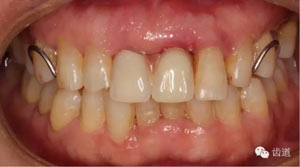

初診照片(正面照)

臨床檢查:11,21伸長(zhǎng)1-2mm,松動(dòng)1度,叩(+),21齦緣稍紅腫,唇側(cè)牙槽骨較豐滿,前牙咬合早接觸,中低位笑線,口腔衛(wèi)生一般。

放射檢查:11,21根中三分之一至根尖三分之一處折斷。

診 斷:11,21根折;牙齦炎